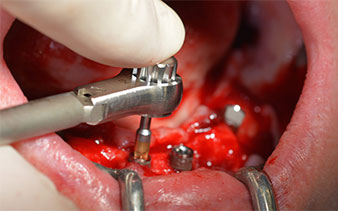

The 64-year-old patient presented with residual dentition of teeth 38, 33 and 43 and a clasp denture in the mandible (Fig. 1 and 2).

Fig. 1

Fig. 2